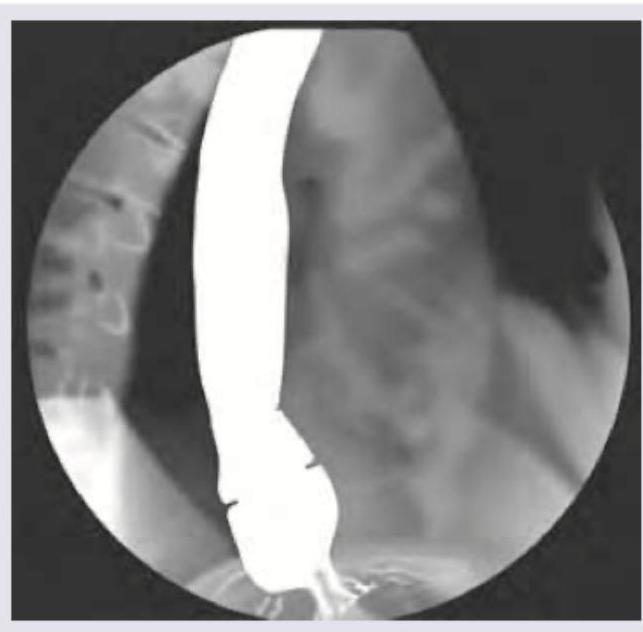

A 45-year-old female patient complains of dysphagia for one year. UGI endoscopy was normal. Diagnosis is: (Recent NEET Pattern 2016-17)

Explanation: ***Diffuse esophageal spasm*** - The image shows a **"corkscrew" or "rosary bead" esophagus**, which is a classic radiographic finding in diffuse esophageal spasm due to uncoordinated esophageal contractions. - Dysphagia in this context, coupled with a normal UGI endoscopy (ruling out mechanical obstruction visible by scope), points to a motility disorder. *Zenker's diverticulum* - This is an **outpouching of the pharyngeal mucosa** occurring above the upper esophageal sphincter. - It would typically appear as a distinct barium-filled pouch on a barium swallow, not the diffuse spasm seen in the image. *Dysphagia lusoria* - This is dysphagia caused by **vascular compression of the esophagus**, usually an aberrant right subclavian artery. - It would manifest as a localized external compression rather than the widespread functional spasm shown. *Esophageal carcinoma* - Esophageal carcinoma would typically present as a **fixed filling defect, stricture, or ulceration** on a barium swallow, often with abnormal mucosal patterns. - The UGI endoscopy would likely show an abnormality if carcinoma were present.

Explanation: ***Cobble stone appearance*** - **Cobblestone appearance** on barium swallow studies is typically associated with **Crohn's disease** affecting the bowel, characterized by deep ulcerations intersected by edematous mucosa. - This image clearly shows severe, disorganized contractions in the esophagus, which is characteristic of a **motility disorder**, not Crohn's. *Corkscrew appearance* - The image distinctly shows a **twisted, irregular contour** of the esophageal lumen, which is well-described as a **corkscrew esophagus**. - This finding is classic for **diffuse esophageal spasm** (DES), where powerful, uncoordinated contractions occur. *Rosary bead esophagus* - This term is another descriptive phrase for the appearance of the esophagus in **diffuse esophageal spasm**. - The appearance resembles beads on a rosary due to the **simultaneous, non-peristaltic contractions** causing segmental narrowing and outpouching. *Pseudodiverticula* - While not true diverticula which are herniations of all layers, the saccular outpouchings seen between the spastic contractions can be described as **pseudodiverticula**. - These are formed by the irregular, forceful contractions transiently distorting the esophageal wall.